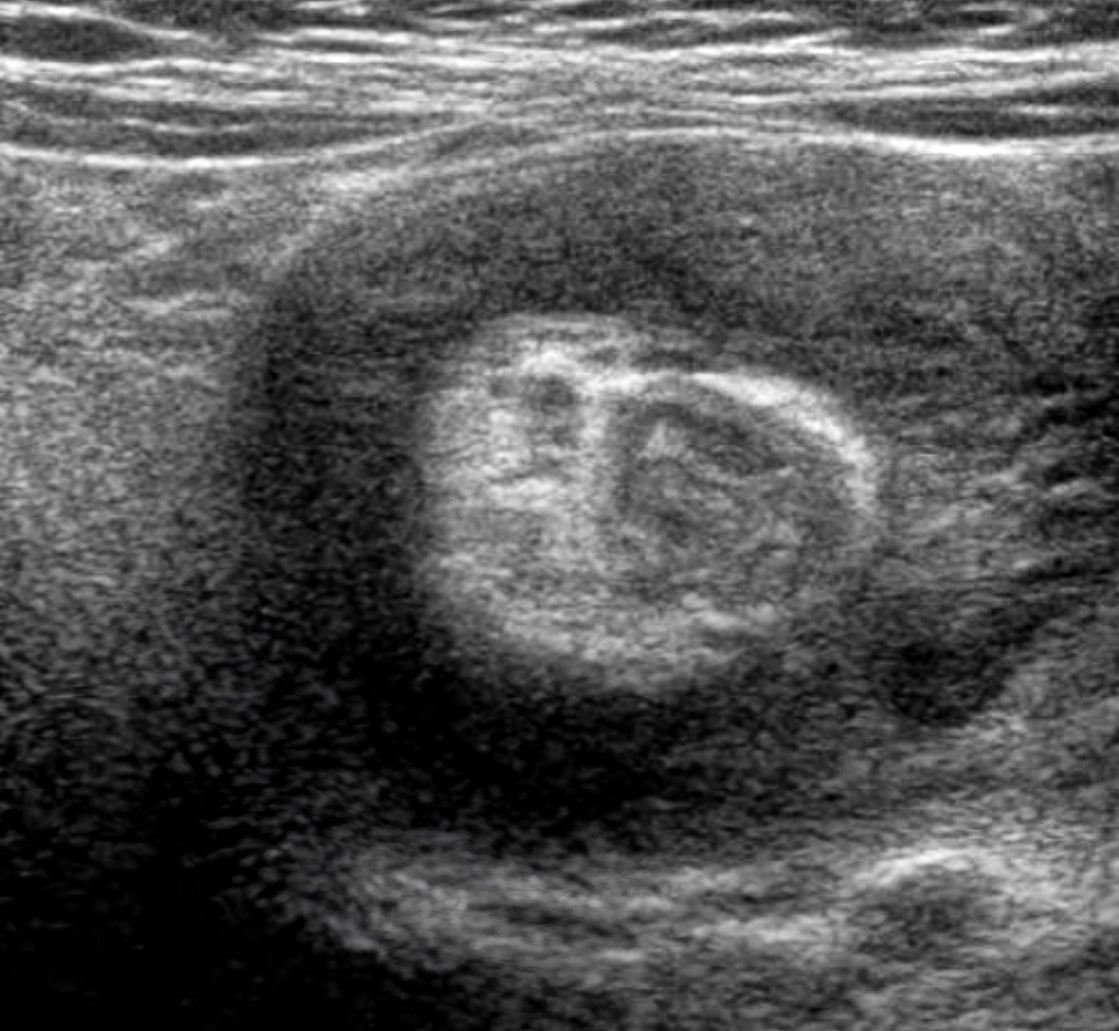

진단을 위해 가장 먼저 복부 X선 촬영을 시행한다. 이를 통해 장관 내의 가스 분포를 확인하거나, 만져지는 종괴의 음영을 확인하여 장중첩증을 의심할 수 있다. 이후, 복부 초음파로 “도넛 사인”과 같은 특징적인 소견을 통해 정확한 진단을 할 수 있는데 장이 말려 들어가 겹쳐진 모양의 단면이 마치 도넛 모양으로 보이기 때문이다.